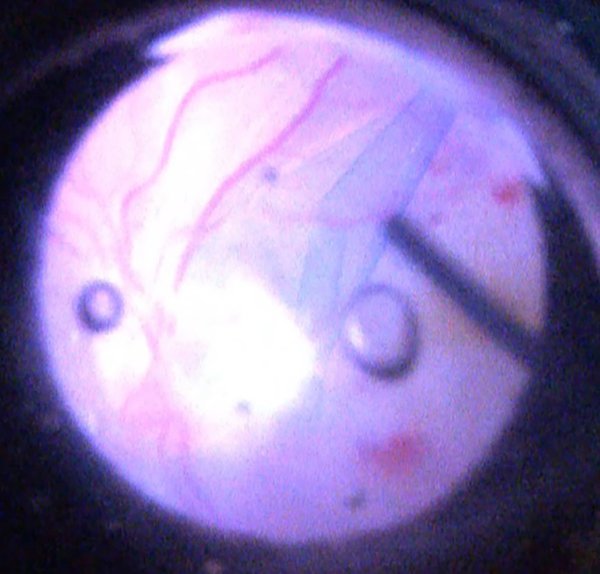

Decidimos realizar tratamiento quirúrgico: vitrectomía por pars plana (VPP) con peeling de membrana limitante interna (PMLI) y aposición de flap sobre el pit, taponamiento con hexafluoruro de azufre y endofotocoagulación peripapilar (figs. 6 y 7).

Figura 6. Imagen intraoperatoria que muestra la confección del flap de membrana limitante interna y su posicionamiento sobre el pit de papila. Acercamiento con lupa de contacto para mácula.

Figura 7. Imagen intraoperatoria con lupa de no contacto que muestra el peeling de la membrana limitante interna y el flap invertido sobre el pit de papila.

En los casos presentados se realizó vitrectomía, inyección de gas y PMLI con técnica de flap de membrana limitante interna (MLI) invertido, posicionado sobre el pit de papila, generando así su cierre y evitando el continuo drenaje de líquido al espacio intra y subretinal. Se ha reportado el uso de diferentes materiales o tejidos para producir el cierre mecánico del pit: MLI, membrana amniótica liofilizada, conjuntiva y/o esclera11, 22.